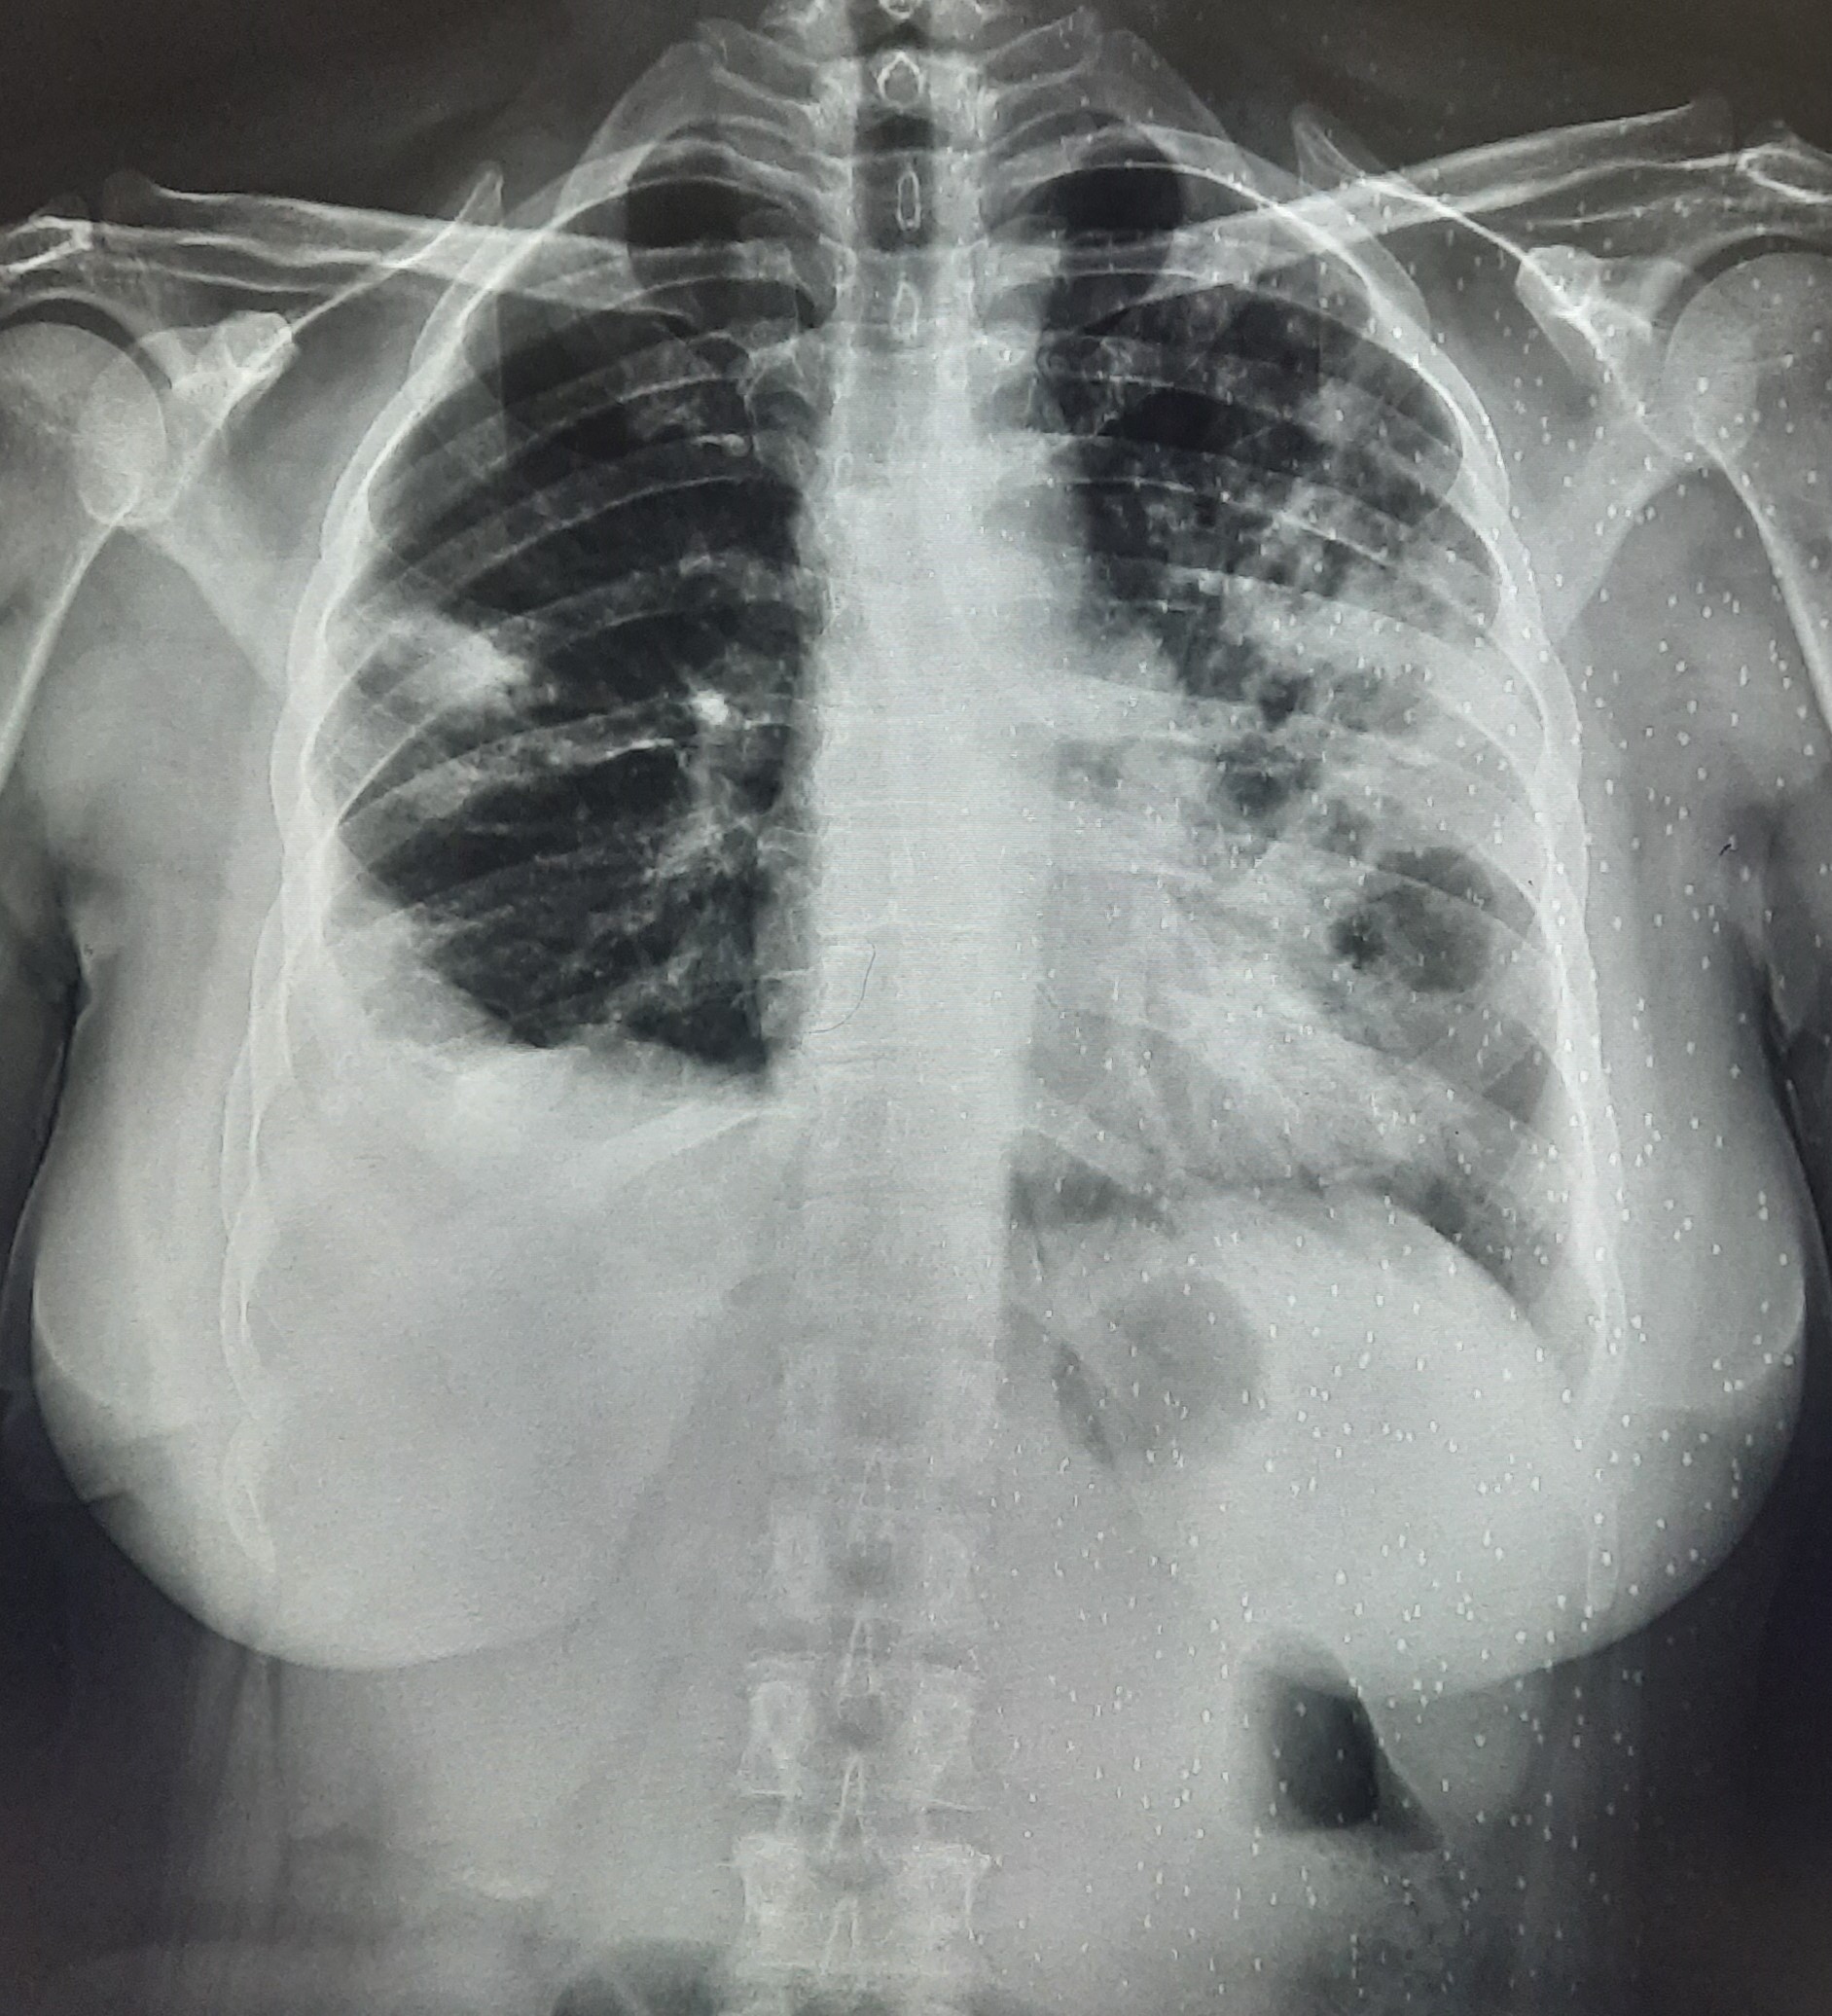

| 292 | IGGMC, Nagpur, Nagpur | P2 | 29-4180 | Geeta Bhonde | Consent taken on Paper | 52 Yrs. |

Provisional Diag : ?

Final Diag : Cardiomegaly |

Non-TB Case (Confirmed) | Abnormality visible on x-ray |